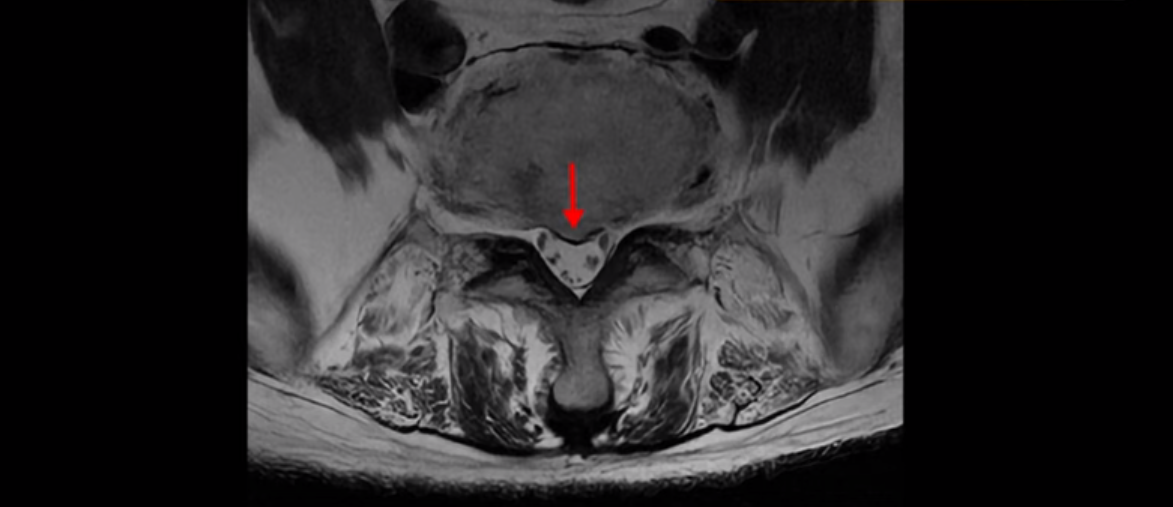

기립근의 지방화도 심합니다. 또 3번 4번 마디에서는 신경가지가 빠져나가는 추간공이 왼쪽, 오른쪽 모두 많이 좁아져 있습니다.

이런 이유로 이 환자분은 왼쪽 다리는 마비가 생겨 힘이 빠지고 오른쪽 다리에는 심한 방사통이 있어서 휠체어까지 타야 하는 상태가 되었습니다. 이렇게 심하니까 대학병원에서 여러 마디 나사를 박는 유합술을 권유 받으셨는데요.